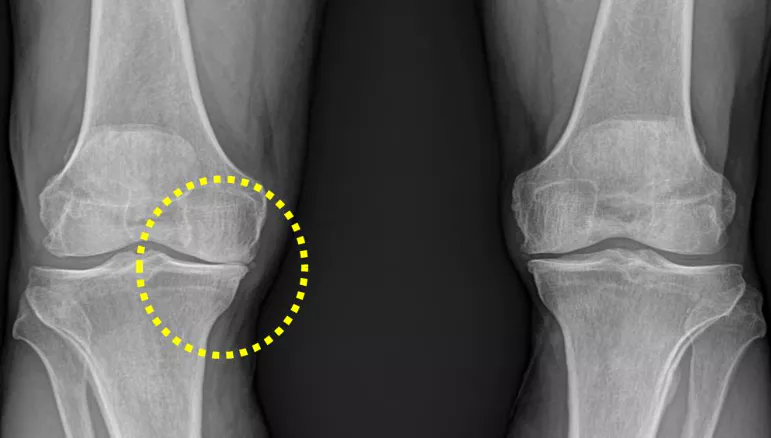

무릎 관절염은 많은 사람들에게 영향을 미치는 흔한 관절 문제 중 하나입니다. 이러한 질환이 있는 환자들은 적절한 운동을 통해 무릎 관절을 더욱 강화하고 통증을 완화하는데 도움을 줄 수 있습니다. 이 글에서는 무릎 관절염에 좋은 운동 10가지 및 주의사항에 대해서 자세히 살펴보겠습니다.